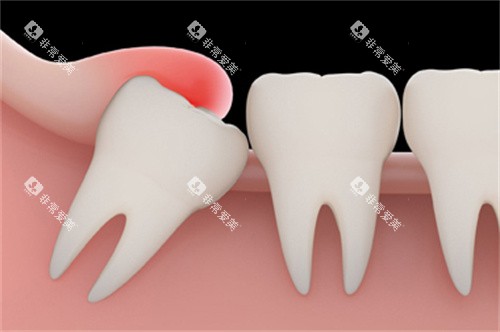

阻生智齿:按生长角度划分的价格梯度

阻生智齿因生长空间不足,出现倾斜、水平或垂直阻生等状态,需切开牙龈、分牙甚至去骨才能拔除,价格随难度递增。

近中阻生智齿:700-1500元起

牙齿向邻牙方向倾斜生长,常顶住邻牙牙根,拔除时需避免损伤邻牙及牙周组织,对医生操作精又准度要求较高,收费随之上升。

水平阻生智齿:800-1800元起

牙齿横向生长,牙冠与邻牙平行,拔除需切开牙龈、去除部分牙槽骨并分割牙齿,手术耗时较长,是阻生智齿中较复杂的类型。

钦州本地诊疗数据显示,水平阻生智齿因易引发邻牙龋坏或牙周炎,就诊需求较高,其收费也因机构设备差异存在200-300元的浮动空间。